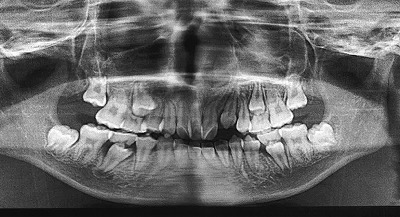

今日のX線を見てわかると思うが、全ての乳歯が永久歯に生え変わっている。

比較に2年前のそれを見てみるとよくわかるだろう。

として、2つのX線像を並べて下さった。

これ、2年前。

確かに。

よくわかります。

今回、歯は横一線。

2年前、歯の下に歯がある、乳歯の下の永久歯だ。